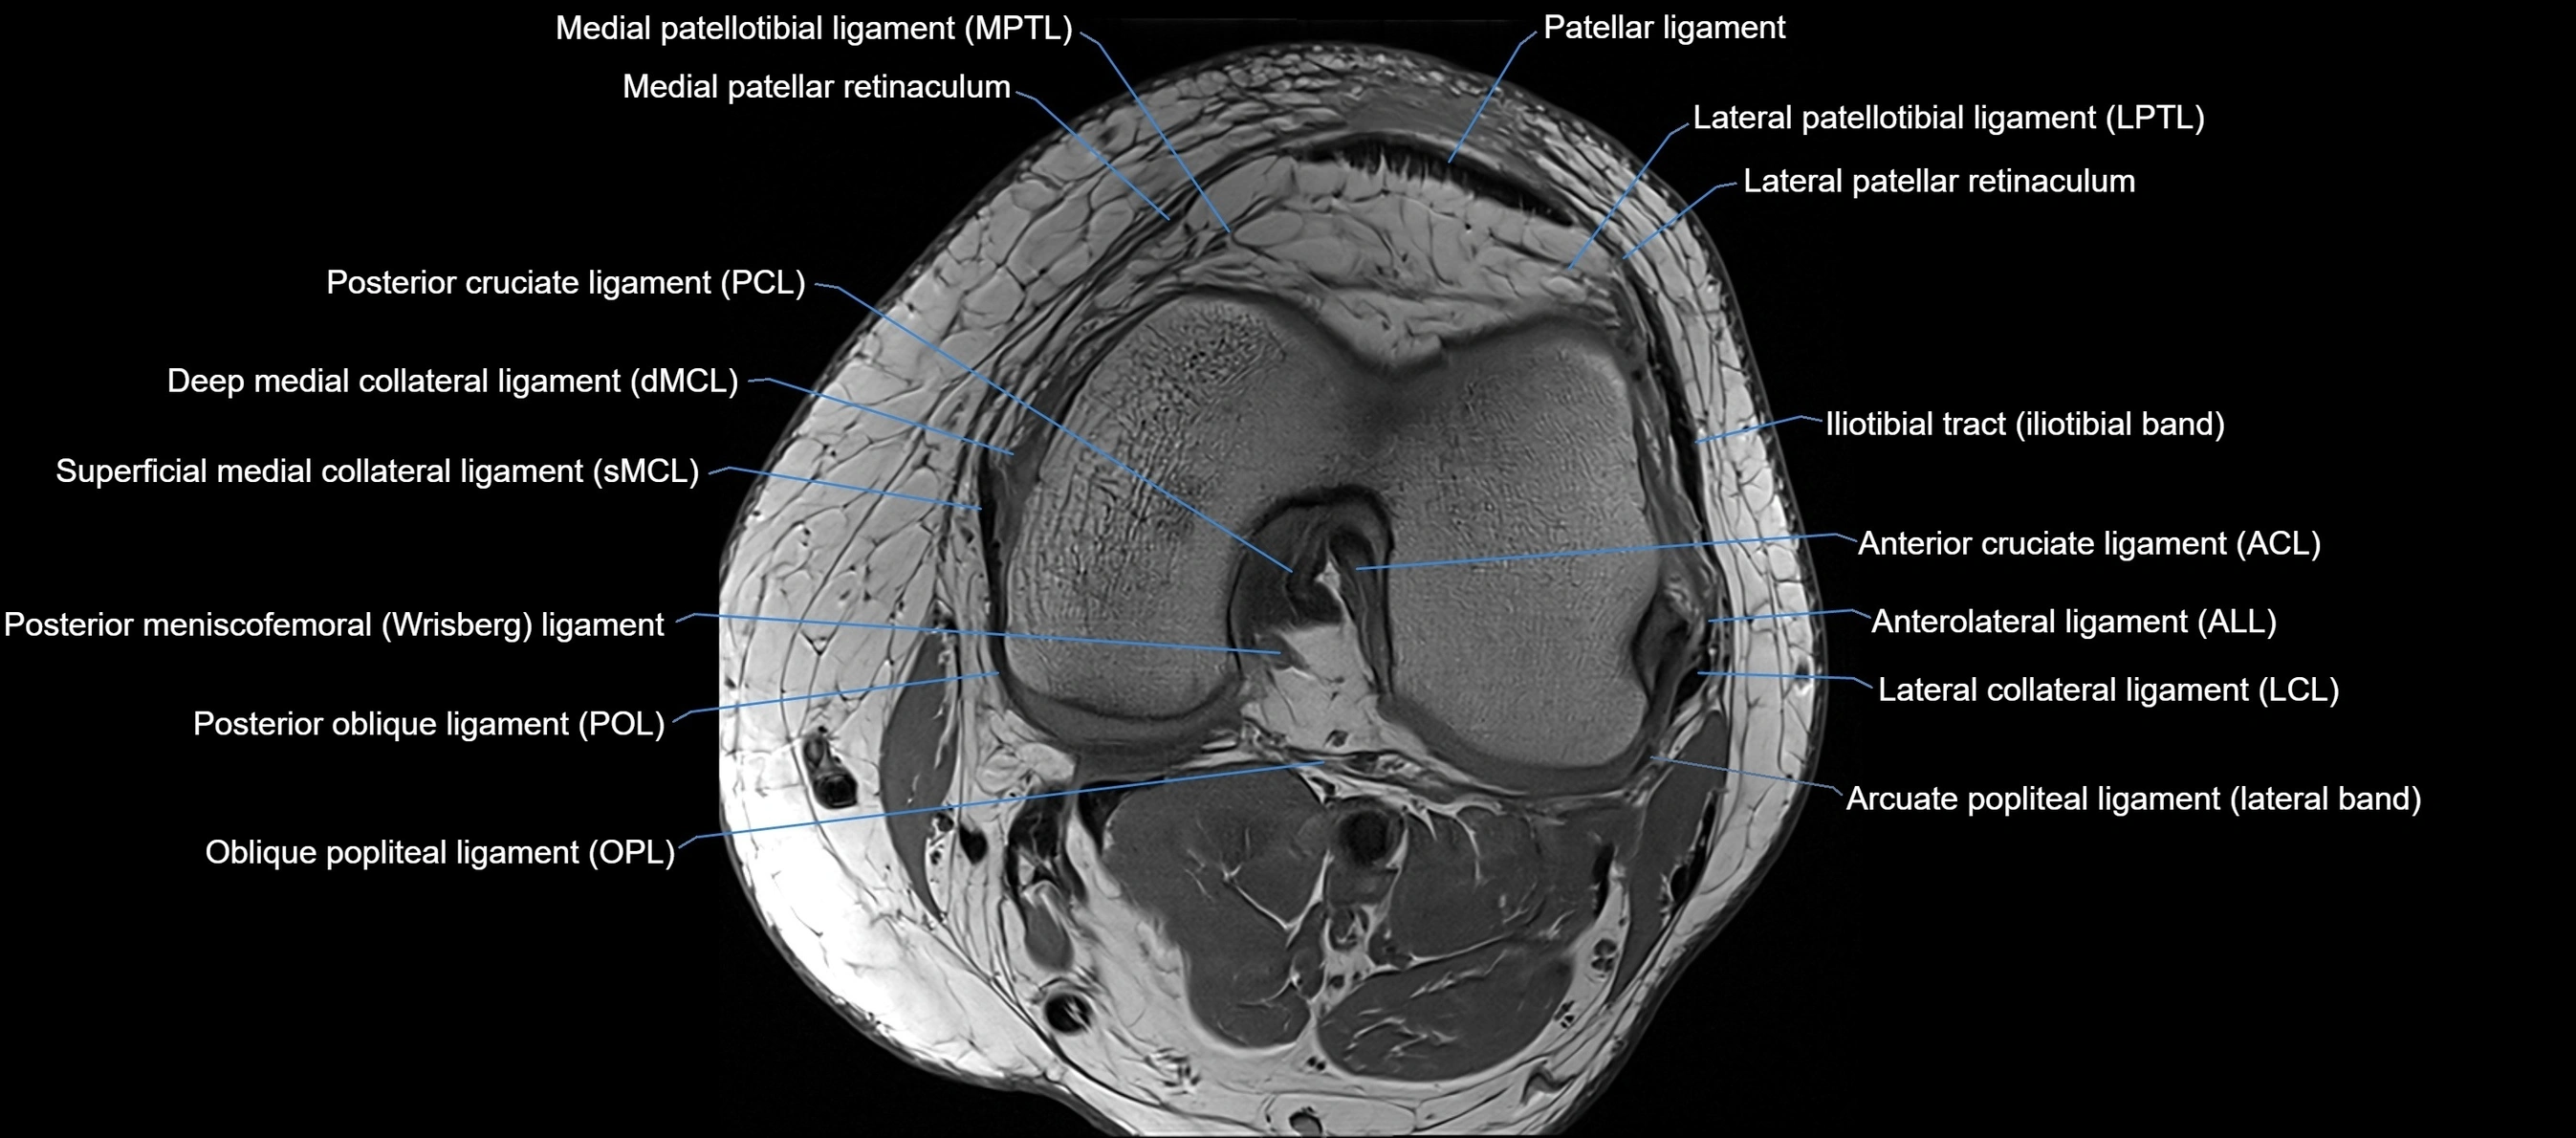

MRI images

image